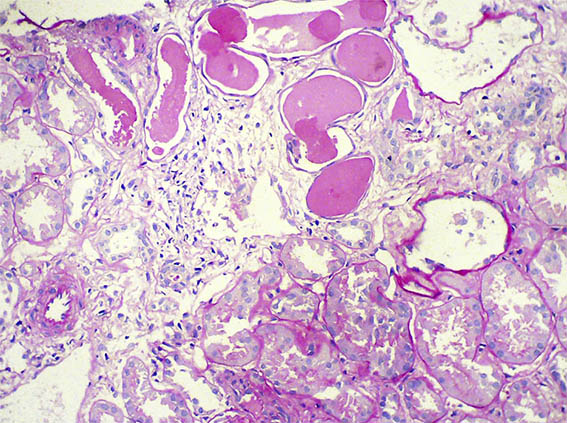

Figure 2. H&E, X100.